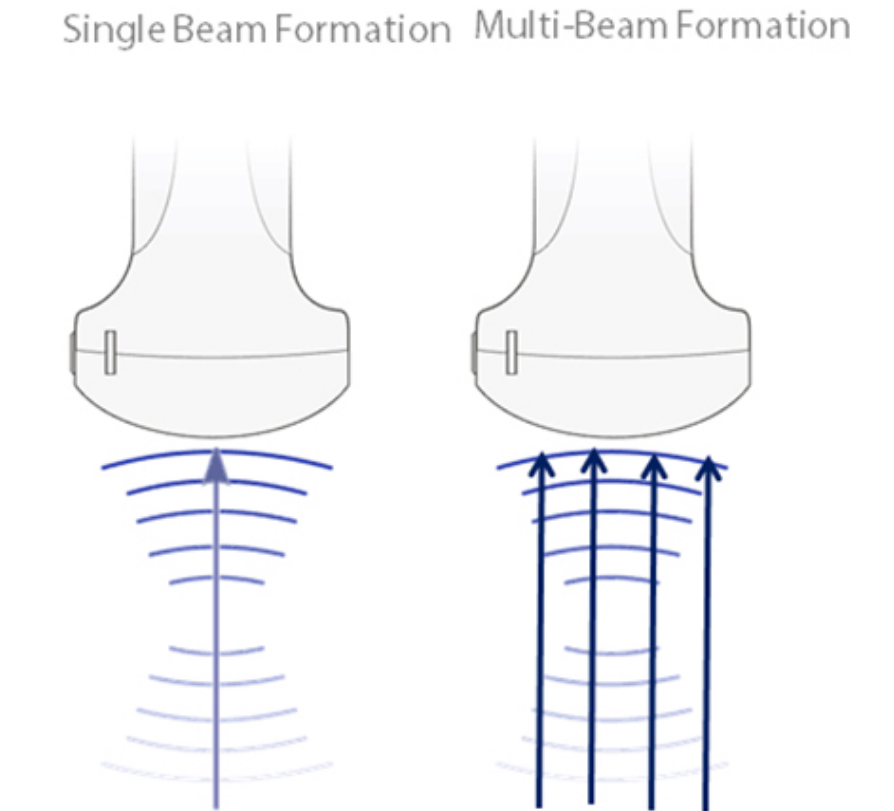

Multiple Beam Formation

Satu berkas yang ditransmisikan akan dikembalikan maksimum 4 kali, sehingga menghasilkan resolusi waktu luar biasa dan laju bingkai lebih tinggi..